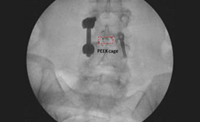

Izquierda: antes y después, espondilolistesis grado II tratada con implante percutáneo por el Dr. Morgenstern. Derecha: Implante percutáneo en canal estrecho

Implantes dinámicos percutáneos para lumbalgia crónica por síndrome facetario